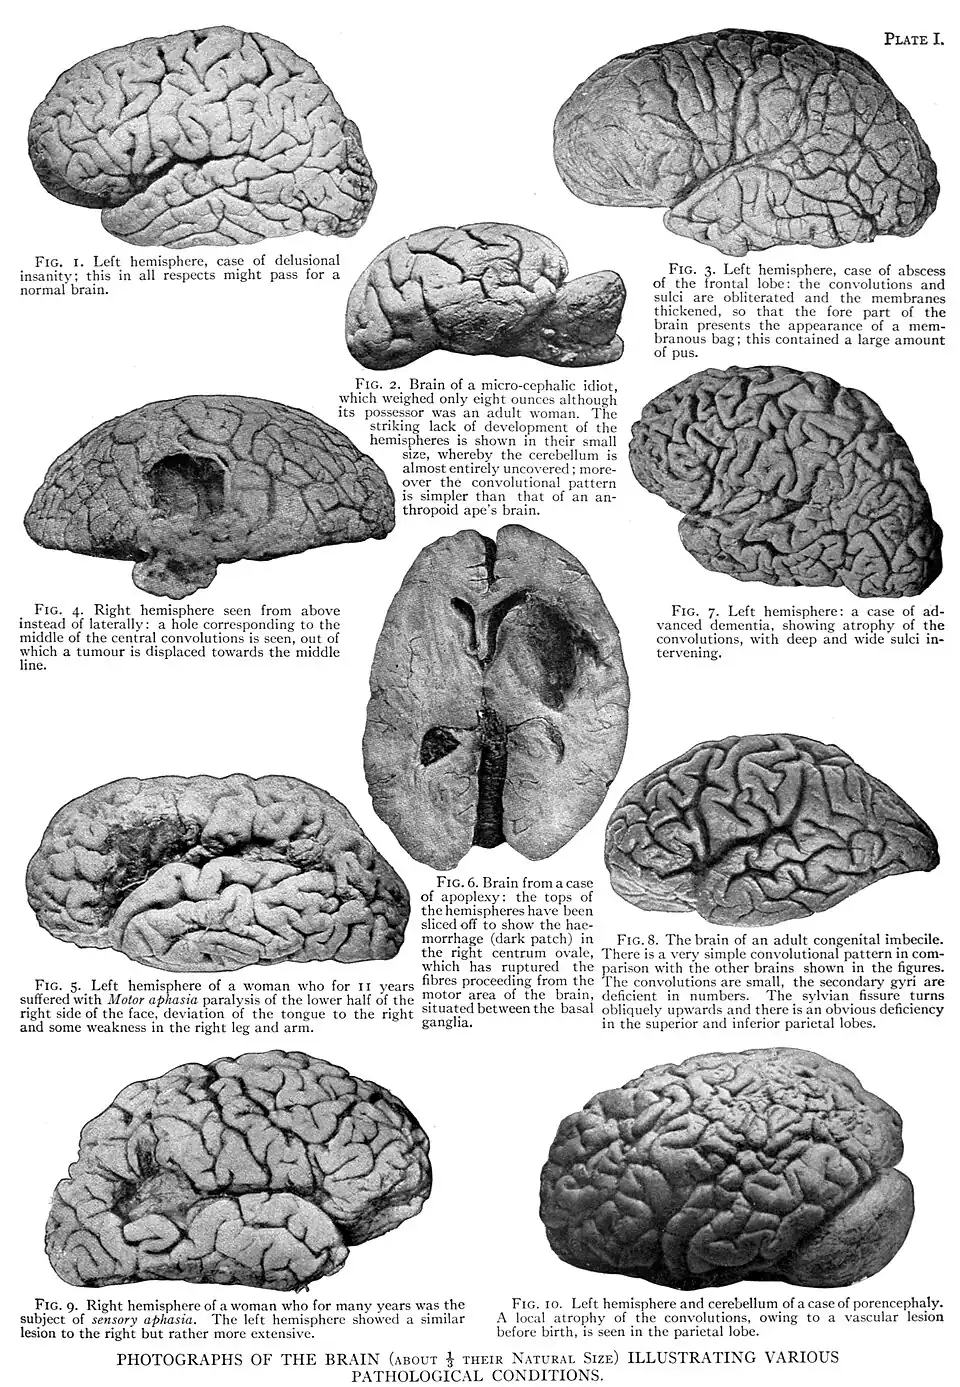

Direct injury or a fall fracturing the skull, driving the fragments into the brain, will cause direct destruction of the nervous tissue; but wounds and diseases of the enclosing and supporting structures, if producing simple non-infective inflammation, give rise only to such symptoms as accord with the nerve structure irritated or destroyed. Should, however, the wound or diseased structure become infected with micro-organisms, the disease spreads and becomes generalized likewise the symptoms. Of all the causes of infective inflammation, middle-ear disease, on account of its frequency and insidious onset, is the most important. It is very liable, when neglected, to be followed by a septic meningitis, encephalitis and brain abscess, the most frequent seat of which is in the adjacent temporal lobe, but it may be in other parts of the brain, e.g. the cerebellum and frontal lobe (Plate I. fig. 3). The peripheral nerves may be destroyed or irritated by direct injury, disease or new growth in adjacent tissues, or they may be involved in the callus thrown out round the seat of a fracture.

Neuroses and psychoses have not hitherto been satisfactorily explained by definite morphological changes in the brain (Plate I., fig. 1). We know little or nothing accurately about the morbid histology of insanity, except as regards the morphological changes met with in cases of amentia and dementia. The conditions of amentia, namely, idiocy and imbecility, are associated with arrest of development of the brain, as a whole or in part, the naked-eye evidence of which may be afforded by small size and simplicity of convolutions of the brain as a whole or in part (Plate I., figs. 2, 8 and 10); and the microscopical evidence by arrest of development, or imperfect development, of structures connected with the higher functions of the mind. namely, the association neurones in the superficial layers of the cerebral cortex (fig. 11). Conditions of dementia, primary or secondary, are associated with progressive decay and atrophy of the superficial layers of the grey matter of the cortex, and nakedeye evidence thereof is afforded by partial or general wasting of the cerebral hemispheres, accompanied with thickening of the pia-arachnoid membrane, atrophy of the convolutions, and with deepening and widening of the intervening sulci (Plate I., fig. 7).